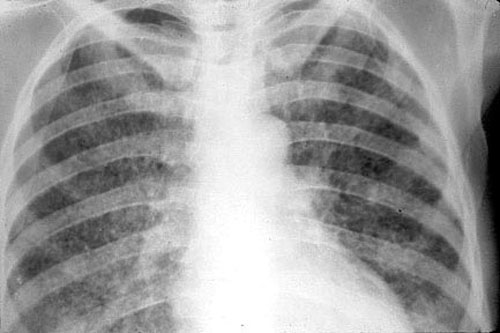

image

Инфильтративная форма

Это наиболее распространенная форма туберкулеза, которая встречается более чем в 60 % случаев. Она характеризуется распространенным некрозом (гибелью) ткани легкого. В зависимости от того, что показывает флюорография легких, выделяют несколько подтипов инфильтративного туберкулеза:

• круглый инфильтрат — затемнение овальной или округлой формы в верхних отделах легких, чаще всего под ключицей;

• облаковидный инфильтрат — тень однородной структуры с неровными границами;

• краевой инфильтрат — тень имеет форму треугольника, вершина которого направлена к корню легкого;

• дольковый инфильтрат — представляет собой группу слившихся очагов различной плотности;

• лобит — тень больших размеров, охватывающая целую долю легкого, имеет неоднородную структуру.